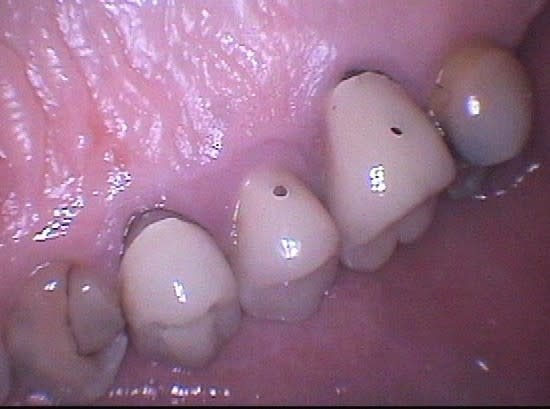

Ceci est un exemple de traitement de poches par photo-ablation en une seule séance en mode continu sans contact, cette technique diffère des traitements par lasers fibrés.

Après sondage et traitement médical, la gencive non attachée est volatilisée avec stérilisation et hémostase immédiate. La cicatrisation est rapide et la ré-attache se réalise en quelques jours, laissant dégagés les espaces biologiques afin de permettre un entretien aisé par le patient, la texture de la gencive prenant un aspect en peau d'orange et reformant progressivement un feston.

Marc, évidemment qu'il s'agit de gingivectomie, je dirais même plutôt gingivoplastie, la gencive est sculptée par le laser plus fidèlement qu'avec un bistouri ou une fraise car il suit exactement le trajet et la profondeur de chaque poche sans sectionner à l'emporte pièce.

J'ai rajouté les photos vestibulaires sur mon premier post, les poches étant un peu moins profondes qu'en palatin.